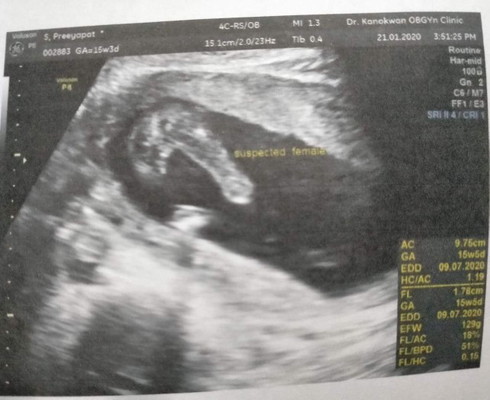

รูปอัลตร้าซาวด์

แม่ๆช่วยดูหน่อยคับว่าเพศญ/ช หมอบอก80%เป็นผู้หญิงคับ

น่าจะหญิงจ๊ะ ยังไงรอหมอฟันธงนะจ๊ะ

หญิงค่ะ